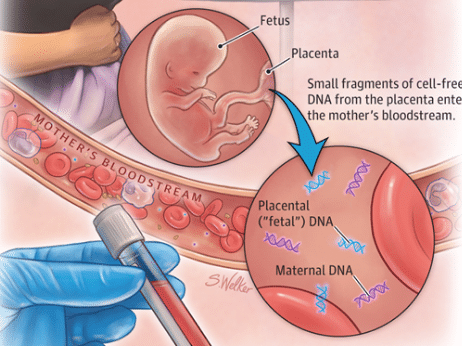

Diagnóstico Não Invasivo das Trissomias do 13 e 18

ARTIGO PUBLICADO DEMONSTRA QUE COM TÉCNICA ADEQUADA É POSSÍVEL FAZER DIAGNÓSTICO PRÉ-NATAL NÃO INVASIVO DAS TRISSOMIAS DO 13…